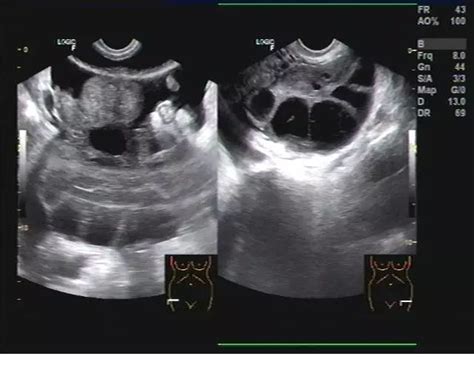

卵泡黄素化是转成囊肿了吗(图片来源网络)

正常情况下成熟卵泡会很快排卵,当排卵后就会消失。但当超声显示成熟卵泡一直不排卵消失,在持续增大,也无直肠子宫陷凹游离液,这就表示卵泡黄素化了。

卵泡发育成熟了,若是因内分泌失调,体内激素不足导致卵泡不能破裂,就会变成卵泡黄素化囊肿,这种囊肿形态规则,囊壁菲薄,且囊液透声好,它多是生理性的,可自行消失,不需要干预治疗。